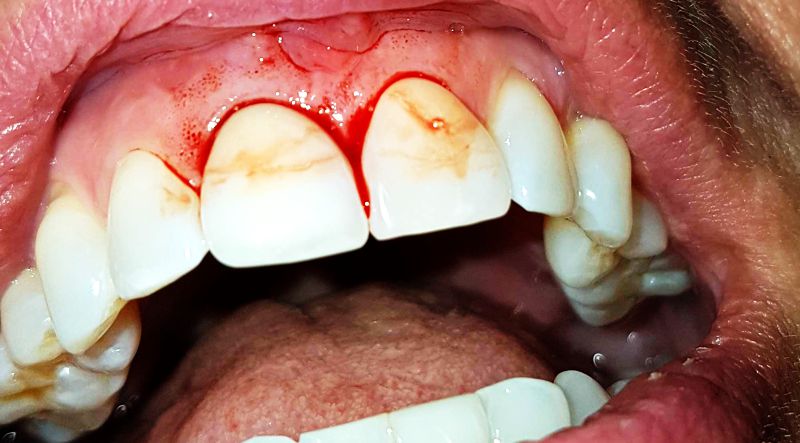

Veränderungen im Zahnfleisch: Rötungen, Schwellungen, Blutungen oder Rückgang des Zahnfleisches können Anzeichen von Zahnfleischerkrankungen sein, die unbehandelt zu weiteren gesundheitlichen Problemen führen können.

Die Zahnhälse sind gerötet und empfindlich, bluten rasch.

Das Zahnfleisch ist in der Regel widerstandsfähig, wenn man bedenkt, welche Strapazen das Zahnfleisch manchmal aushalten muss, wenn gewissen Speisen gekaut werden. Jede Art von Blutung ist pathologisch, kann aber vom einfachen Zahnstein über Karies bis hin zu den toxischen Zähnen reichen.

Hier ist ein wurzelbehandelter Frontzahn durch die Verfärbung des Zahnfleisches zu erkennen.

Heftige Blutung nach Sondierung dieses Zahns. Die Blutung verteilt sich auf auf die gesunde Zähne.